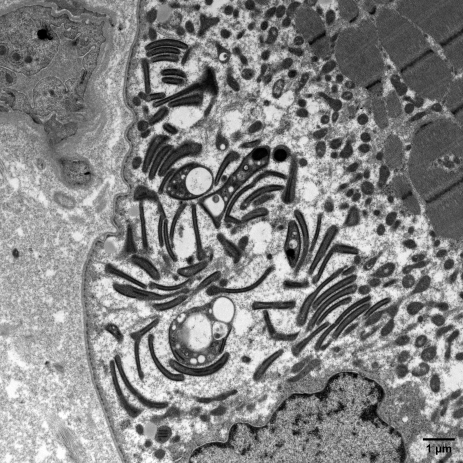

Electron micrograph showing abnormal mitochondria